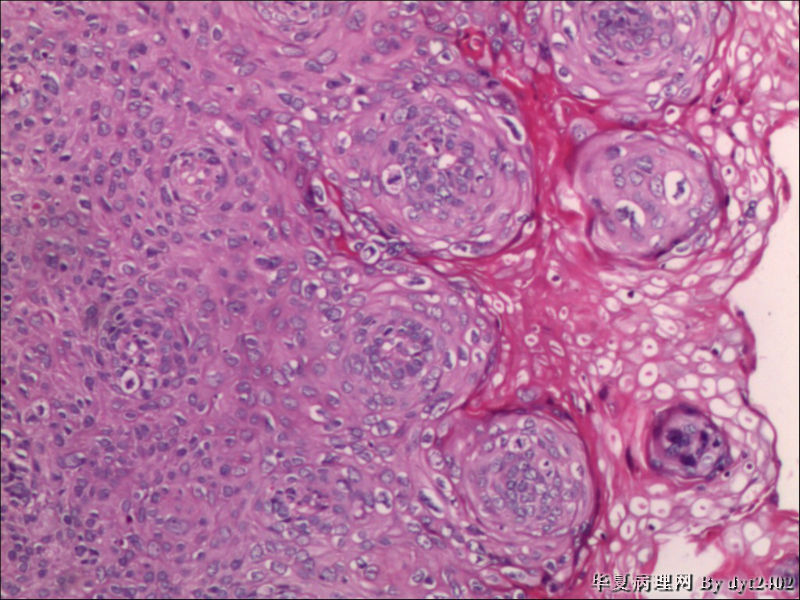

四点中三点是CIN iii,另一点怀疑有更重病变

这个病人是44岁,去年11月底阴道脱落细胞、TCT均见细胞异常,建议活检,病人犹豫,接着单位组织到外院体检时做阴道镜正常,后霉菌感染,此时宫颈未涂醋肉眼看还光滑,直至今年3月来做活检,事前做白带检查又见异常细胞,宫颈未涂醋见后上唇白上皮,涂醋酸后上下唇都有厚白上皮,镶嵌,夹活时上皮剥脱,未能夹到间质,阴道镜医生说至少有CIN III 到原位癌了。。镜下其中3点CIN III无疑,唯有9点处如6、7、11、14等所示结构,但我未见间质浸润,不能说是浸润癌,不知道有没基底细胞样鳞癌的可能,我发了个原位癌不除外深部有更重病变,。

就是说图片中的,大部分是9点的组织,有没到癌的问题